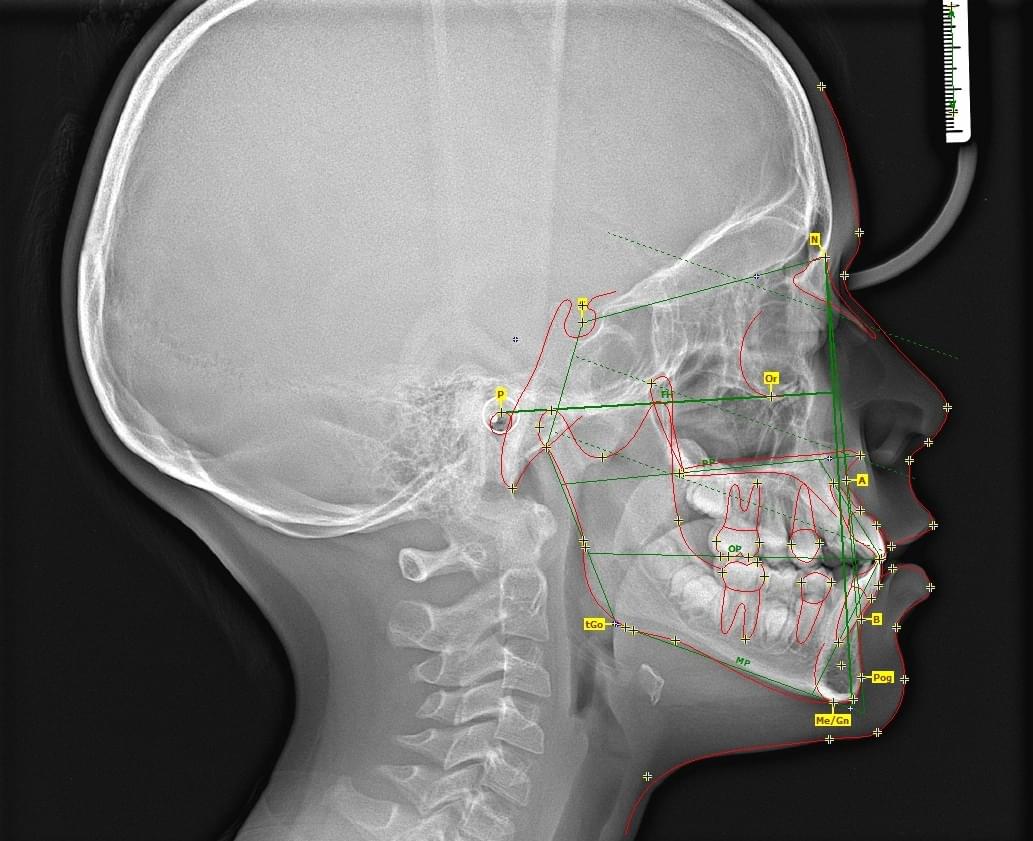

CBCT Maxilofaciální diagnostika